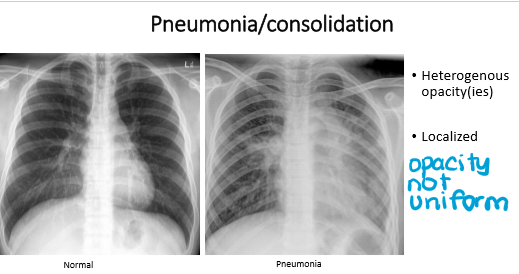

whats the dx for these pics?

Left: normal

Right: pneumonia

pneumonia has ________ opacity

It is (localized/general)

pneumonia

heterogenous

localized